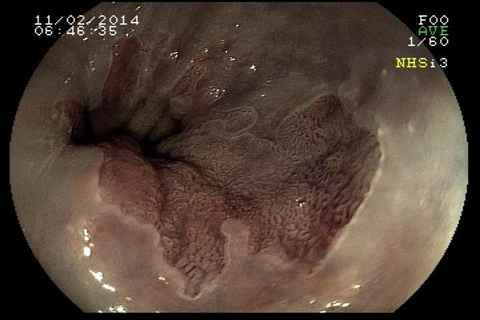

O que é Esôfago de Barrett?

Esôfago de Barrett é uma doença na qual há uma mudança anormal na mucosa do esôfago distal. A doença é causada principalmente pela exposição prolongada ao conteúdo ácido proveniente do estômago e está relacionado a um risco aumentado de câncer do esôfago. Esôfago de Barrett ocorre quando as células normais da porção inferior do esôfago são substituídas por um tipo diferente de células (semelhantes às do estômago). O Esôfago de Barrett normalmente é causado pelo refluxo gastroesofágico (RGE). Portanto, esta substituição das células do esôfago pelas células do estômago, muitas vezes é vista como um mecanismo de proteção ao ácido (as células do estômago são preparadas para resistir à acidez). É importante salientar que a maioria das pessoas que tem RGE nunca desenvolverão o Esôfago de Barrett, mas algumas podem desenvolver.Quais são os sintomas do Esôfago de Barrett?

Como detectar o Esôfago de Barrett?

O diagnóstico de Esôfago de Barrett é feito através da endoscopia digestiva alta com biópsia da área suspeita. O médico vai examinar com detalhes a região da transição entre o esôfago e o estômago e, se houver a suspeita de um epitélio anômalo na região, serão coletadas biópsias para análise no microscópio. A inspeção do Esôfago de Barrett deve ser realizada por endoscopista experiente e com aparelho de alta definição, para capturar detalhes suspeitos da mucosa.

Qual o risco do Esôfago de Barrett virar câncer?

Uma complicação do Esôfago de Barrett é que, com a agressão contínua do ácido no epitélio do esôfago, podem surgir células pré-malignas (displasias) que eventualmente podem crescer e virar um câncer invasivo. Estas lesões pré-malignas não costumam provocar sintomas, daí a importância de um acompanhamento médico. No entanto, a progressão do Barrett para um câncer é bastante incomum. Estudos que seguiram pacientes com Esôfago de Barrett, mostram que o risco de progressão para câncer é menor do que 0,5% ao ano.Como o Esôfago de Barrett é tratado?

Tratamento do Esôfago de Barrett com Radiofrequência

A ablação por radiofrequência usa calor para remover tecido pré-cancerígeno do esôfago de Barrett. A tecnologia do sistema de ablação por radiofrequência é projetada para a remoção de tecido afetado por Barrett, preservando o tecido saudável subjacente.Tratamento do Esôfago de Barrett com Mucosectomia

A mucosectomia é uma técnica empregada para ressecção do Esôfago de Barrett com lesões displásicas visíveis (pré-cancerígenas ou cancerígenas iniciais). Geralmente essa ressecção é realizada através da colocação de ligaduras elásticas, seguido da apreensão e corte com alça de polipectomia. O produto da ressecção é enviado para a análise histológica pelo patologista, a fim de verificar se o paciente está curado e para definir como será o acompanhamento no futuro.O que é gastrostomia endoscópica?